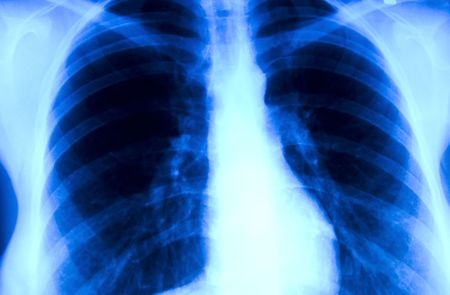

Gruźlica jest chorobą zakaźną, wywołaną przez prątki kwasooporne z grupy Mycobacterium tuberculosis complex – M. tuberculosis, M. bovis i M.

africanum. Światowy dzień walki z tą chorobą ustanowiono 24 marca w celu upamiętnienia wydarzenia z 1882 roku, kiedy Robert Koch ogłosił swoje odkrycie.Mimo postępu w zmiejszaniu liczby zachorowań, gruźlica jest nadal groźna. Według najnowszego raportu Światowej Organizacji Zdrowia

(WHO) i Europejskiego Centrum Kontroli Chorób (ECDC),w latach 2011-2015 w Europie liczba zachorowań na gruźlicę spadła o 4,3 proc., a liczba zgonów – o 8,5 proc. Jednocześnie o 40 proc. wzrosła liczba przypadków tej choroby u osób z wirusem HIV.